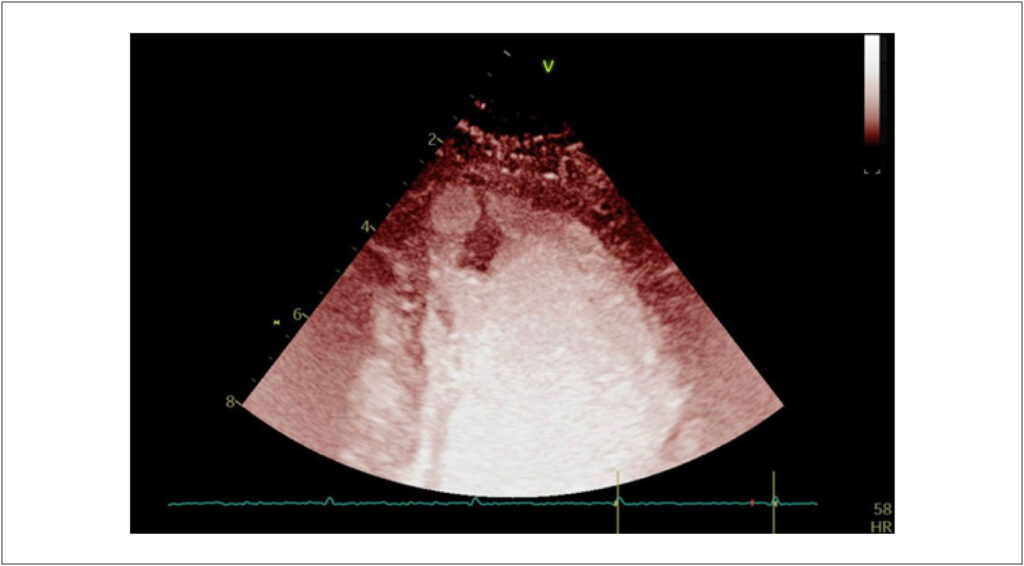

A Importância da Multimodalidade de Imagem no Diagnóstico de um Raro Caso de Fibroelastoma Papilar no Ápice do Ventrículo Esquerdo

O fibroelastoma papilar (FP) é uma neoplasia cardíaca primária rara, benigna, ibnicialmente descrita como achado incidental em autópsias ou cirurgias e ocupa o terceiro lugar entre tumores cardíacos mais frequentes. Acomete principalmente as valvas cardíacas, respondendo por 75% de todos os tumores dessa região e é frequentemente diagnosticado de forma incidental.

A sua apresentação clínica pode variar amplamente, abrangendo desde casos assintomáticos até situações em que ocorre embolização sistêmica causada por trombos aderidos, bem como da fragmentação do próprio tumor. Atualmente, o FP deixou de ser um tumor diagnosticado apenas em autópsias para ser detectado com as novas modalidades de imagens cardiovasculares, permitindo uma abordagem precoce e prevenindo complicações.